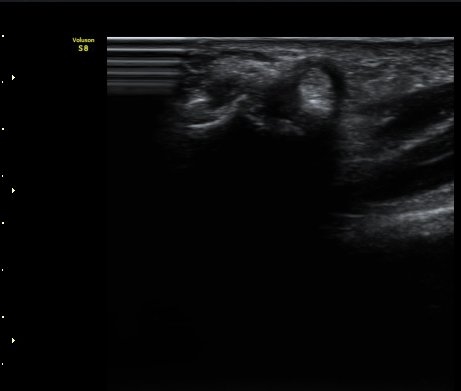

¼Õ°¡¶ô ½ÅÀü ½Ã ºÎÀº ÈûÁÙÀÌ a1ÇÒÂ÷¸¦ Åë°úÇÏÁö ¸øÇÏ°í °É¸°´Â ¸ð½ÀÀÌ °üÂûµÊ(±×¸² 4).

ÈûÁÙÀÌ °É¸®´Â ¸ð½ÀÀº µ¿¿µ»ó(÷ºÎ ÆÄÀÏ)¿¡¼­ ¶Ñ·ÈÈ÷ °üÂûµÊ.